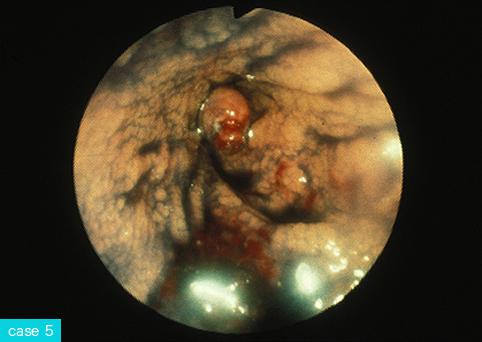

疾病(病理主体)的分类肿瘤样病变/炎症性息肉病

部位(按器官分)大肠/升结肠

检查方法内窥镜

肿瘤最大直径1~9